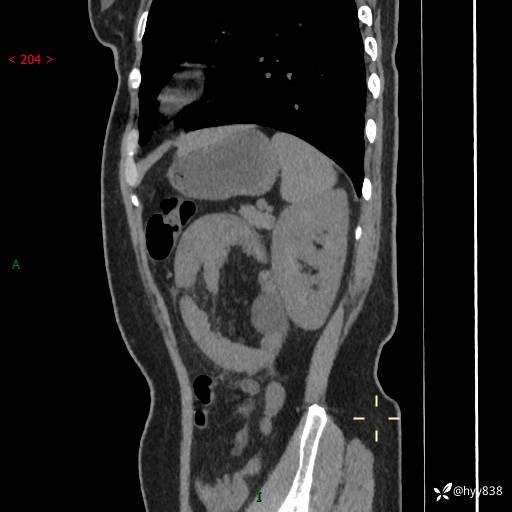

现病史:患者1天前无明显诱因下出现左上腹部及腰背部胀痛不适,阵发性加剧,伴肛门停止排气;无发热,无恶心呕吐,无畏寒发热,无心慌气短等不适,于当地市第二人民医院就诊,行腹部ct检查提示左上腹区肠系膜血管从剧聚集,分布紊乱伴肠管局限性稍扩张积液,不完全性肠梗阻;考虑子宫颈纳氏囊肿,双侧附件区囊状灶;予以抗炎及对症支持等治疗后未见明显缓解,现患者为求进一步治疗来我院急诊就诊,遂以“肠梗阻”收住入院。 病来,神志清,精神可,饮食睡眠不佳,经灌肠后排便2次,小便正常,体力体重无明显变化。

上腹部CT平扫